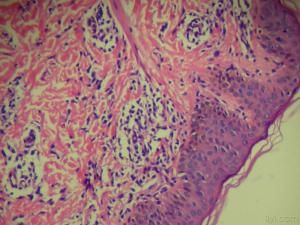

組織病理:小皰位於表皮內,伴海綿形成,有多數嗜酸性粒細胞,水皰間表皮常含有小團的表皮細胞,呈渦輪狀排列及散在的大的嗜酸性透明胞漿的角化不良細胞,真皮浸潤如表皮。疣狀增生處表現棘層肥厚不規則的乳頭瘤樣增生及角化過度,色素沉著處真皮上層噬黑素細胞增多,內含大量黑素顆粒,基底層黑素顆粒減少,有空泡變性。